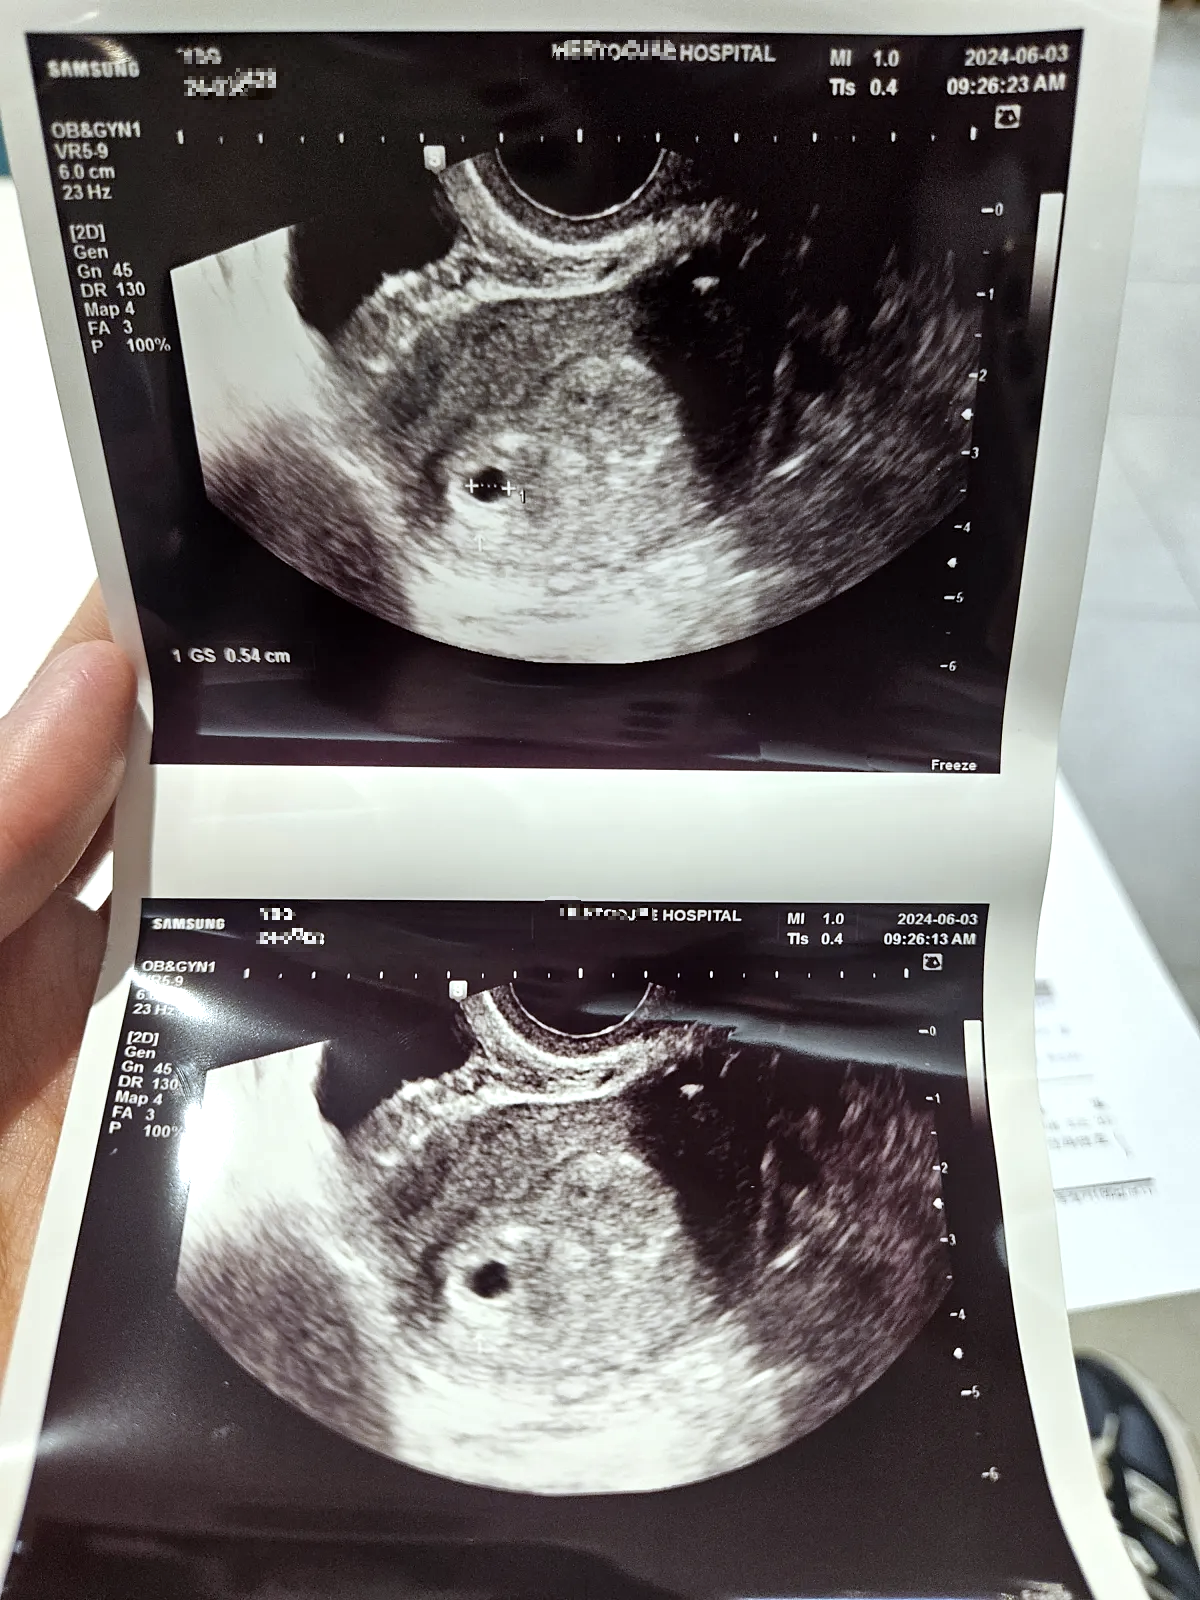

"정말 아기집이 보이네요. 위치도 좋고 지금까지 특별한 문제는 없어요.

난황 확인해야 하니 다음 주 다시 내원하고 일단 축하드립니다. 임신 5주입니다."

0.54cm의 좁쌀만 한 아기집을 확인하고 남편과 눈을 마주하며 한참 기뻐하다가 임신 확인서를 받고 진료실을 나섰다.